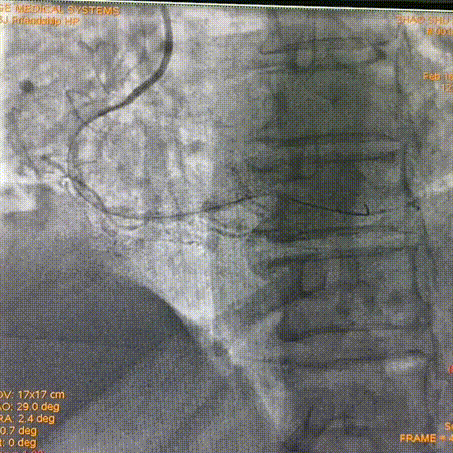

Final Result

Telescope™导引延长导管安心输送长支架-成功输送长支架到位,输送性优异,且无器械剐蹭现象发生。

Telescope™增强支撑力-旋磨后加强支撑,辅助置入支架。

安全挑战钙化病变-重度钙化病变多次旋磨后,无创输送器械。